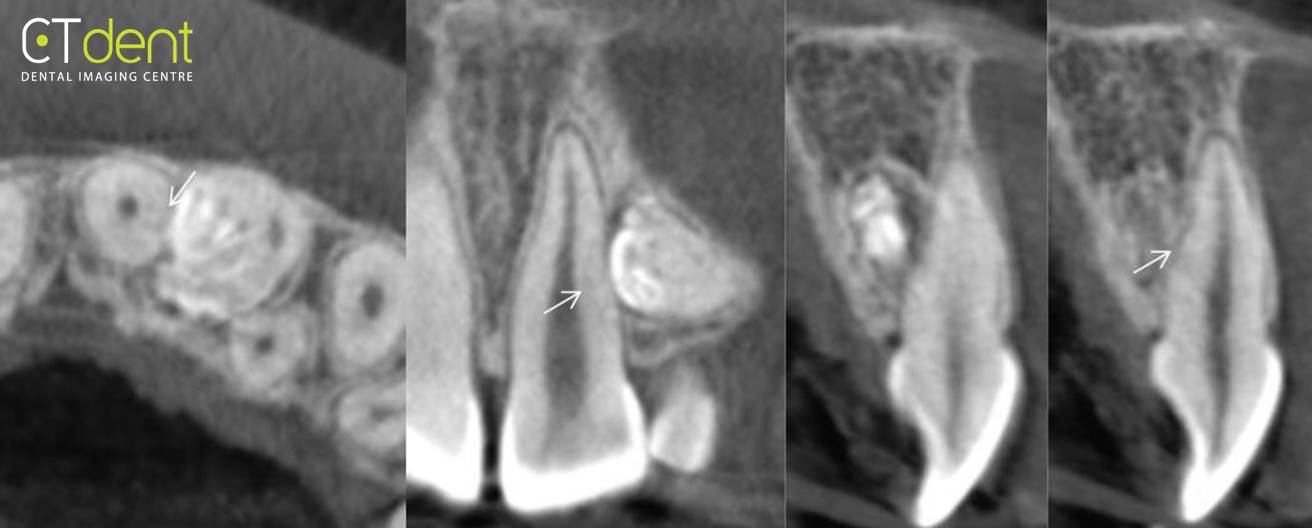

Одонтома нижней челюсти: фотографии и медицинская информация